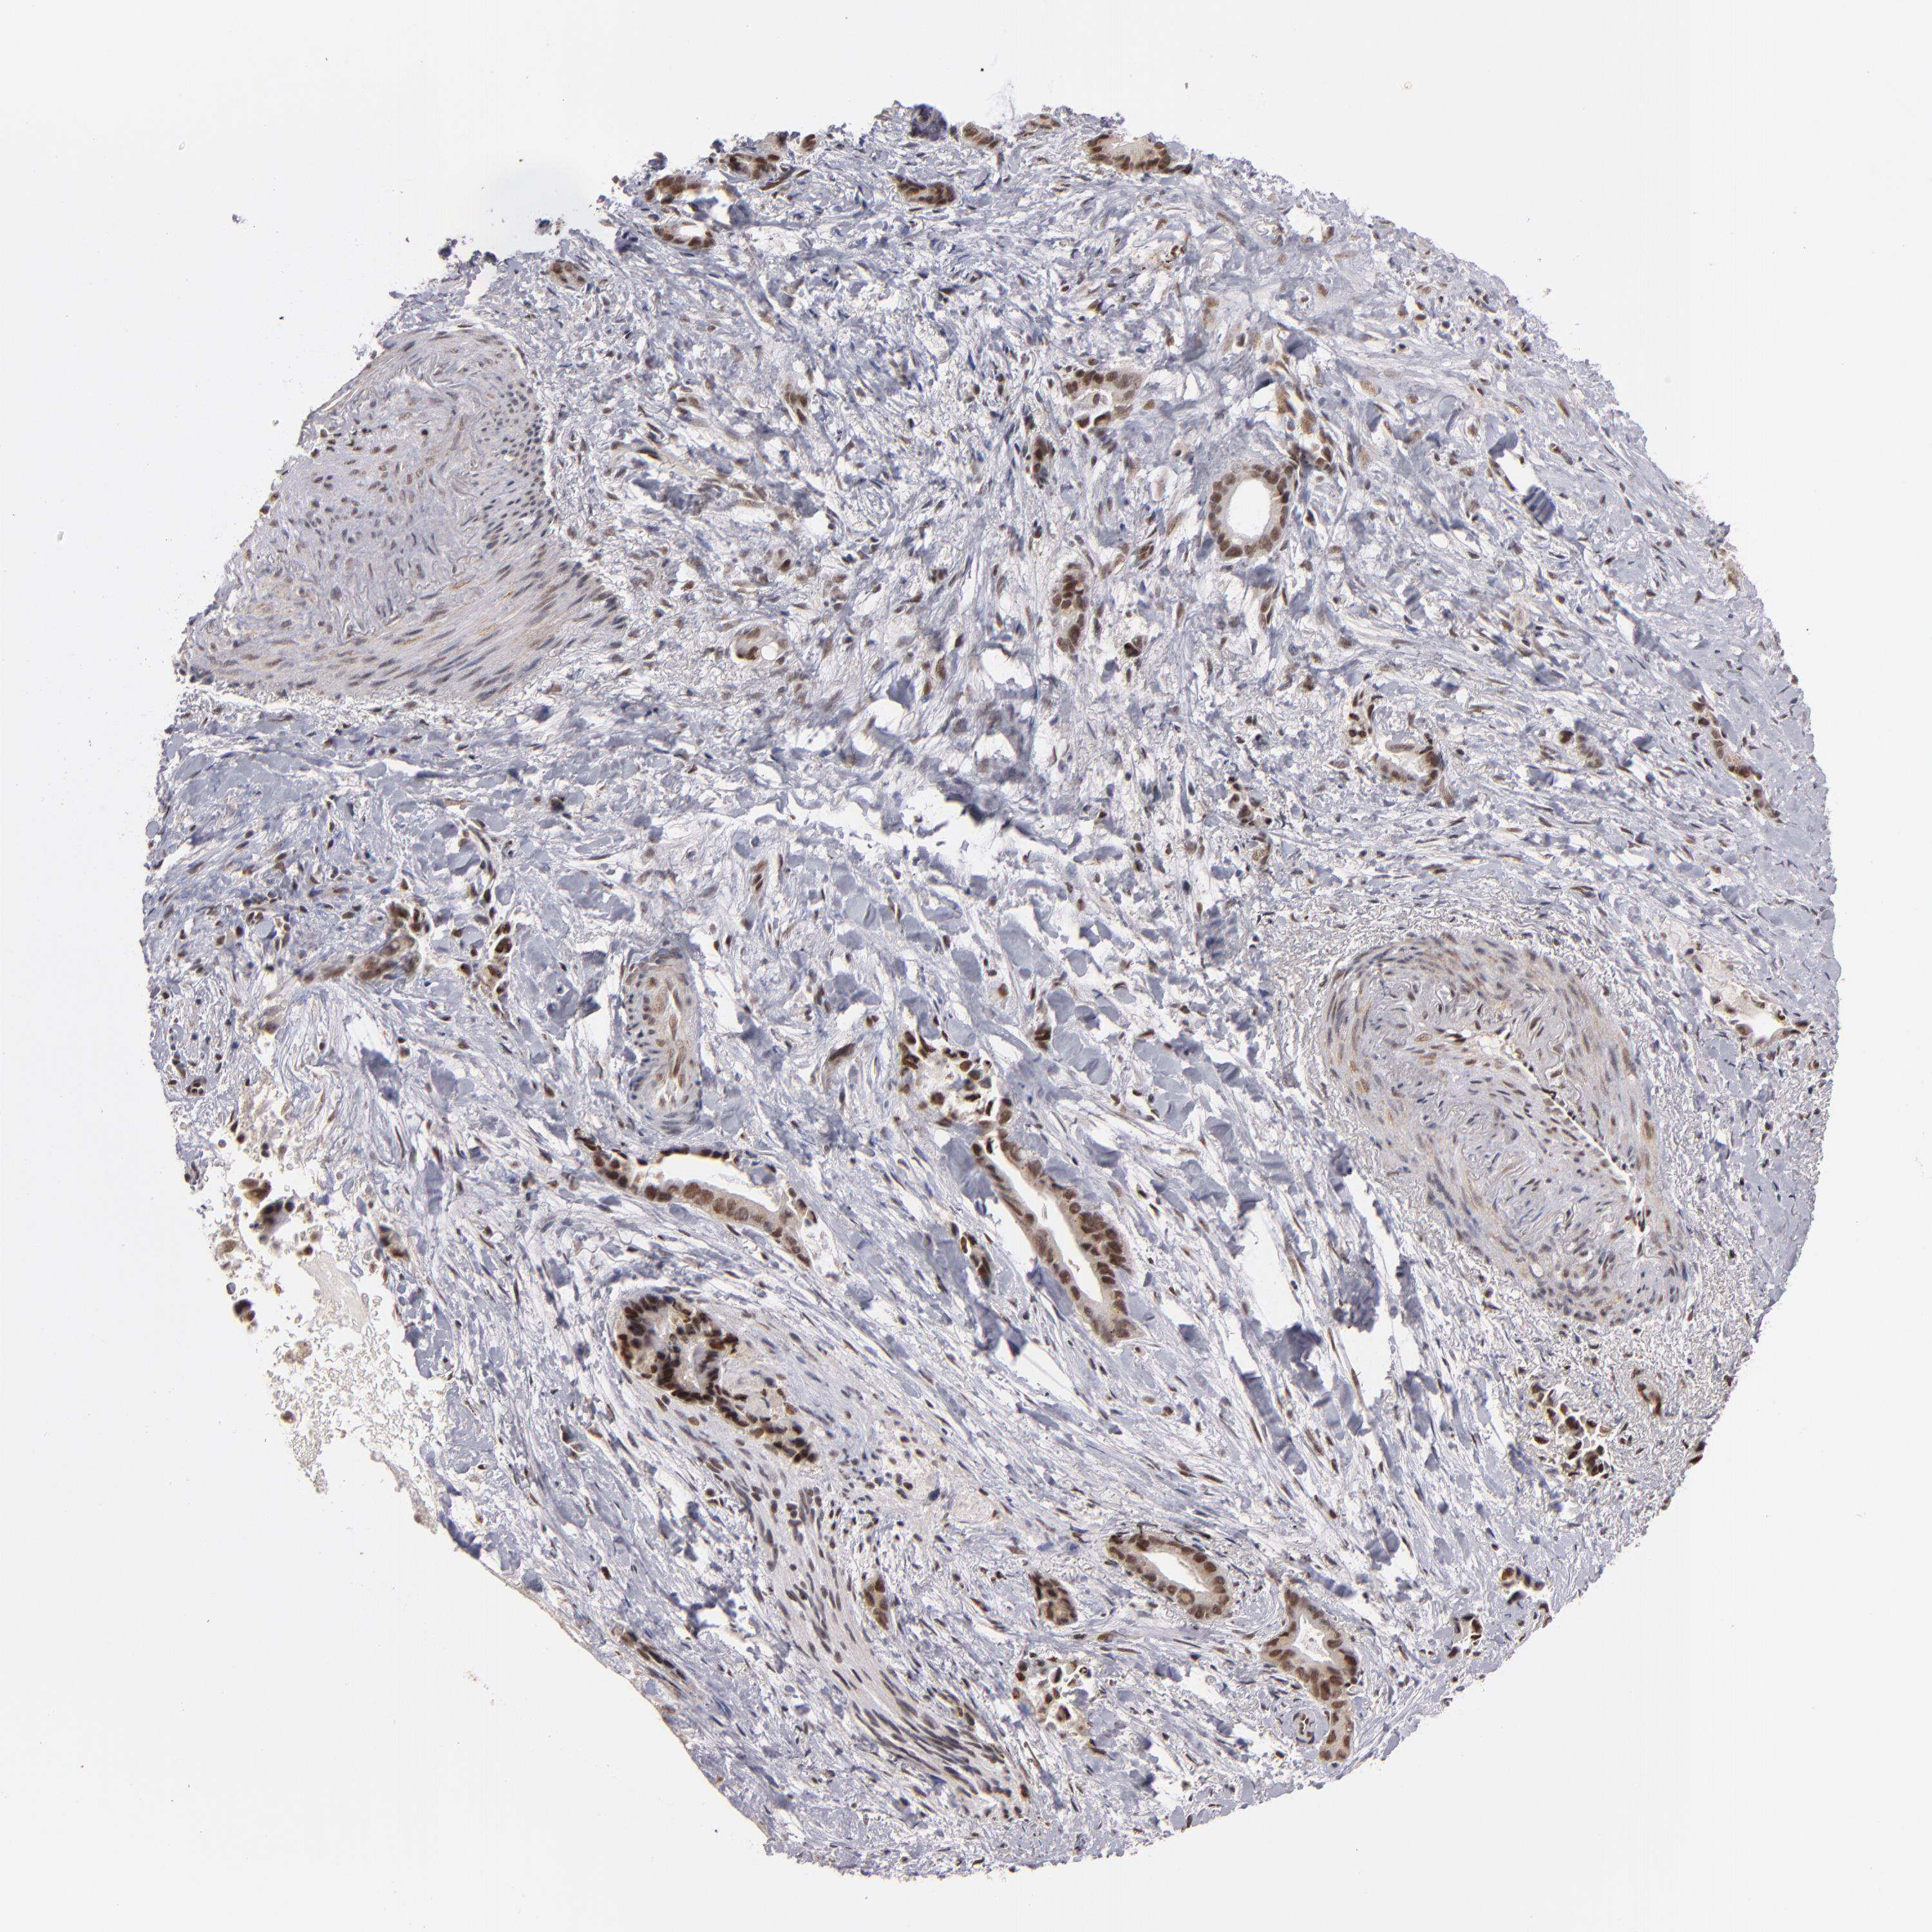

LIVER CANCER - Protein expressioni

A mouse-over function shows sample information and annotation data. Click on an image to view it in a full screen mode. Samples can be filtered based on level of antibody staining by selecting one or several of the following categories: high, medium, low and not detected. The assay and annotation is described here.

Note that samples used for immunohistochemistry by the Human Protein Atlas do not correspond to samples in the TCGA dataset.

Antibody stainingi

Antibody staining in the annotated cell types in the current human tissue is reported as not detected, low, medium, or high, based on conventional immunohistochemistry profiling in selected tissues. This score is based on the combination of the staining intensity and fraction of stained cells.

Each image is clickable and will lead to virtual microscopy that enables deeper exploration of all samples and also displays staining intensity scores, fraction scores and subcellular localization as well as patient and tissue information for each sample.

Antibody HPA001664

Staining

High

Medium

Low

Not detected

Intensity

Strong

Moderate

Weak

Negative

Quantity

>75%

75%-25%

<25%

None

Location

Nuclear

Cytoplasmic/membranous

Cytoplasmic/membranous,nuclear

Cholangiocarcinoma

Carcinoma, Hepatocellular, NOS